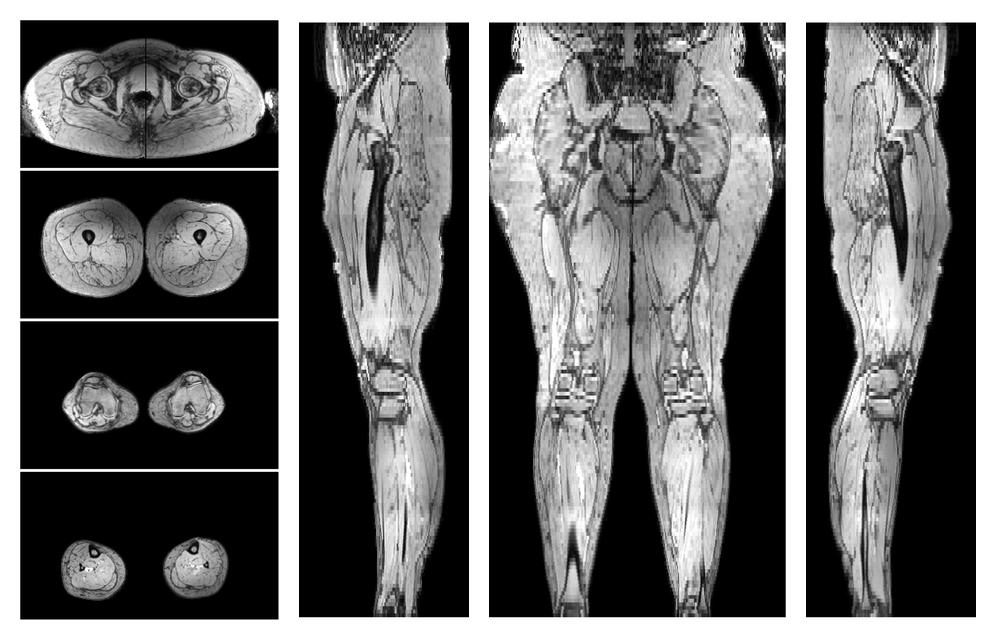

• Out phase image

The out-phase image of the dixon reconstruction for water fat quantification.